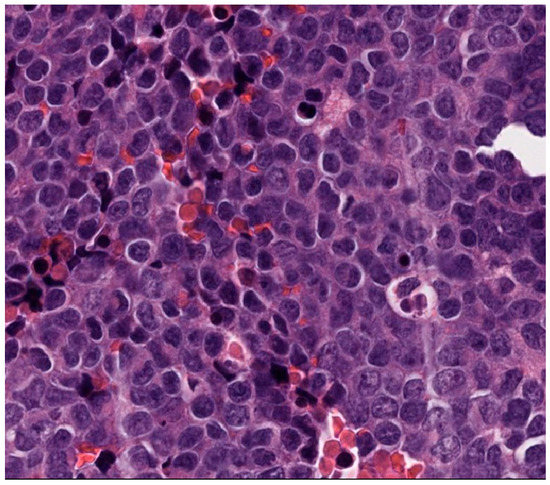

- NanoString gene fusion panel revealed an EWSR1::FLI1 fusion involving exon 10 of EWSR1 and exon 5 of FLI1 (Figure 9).